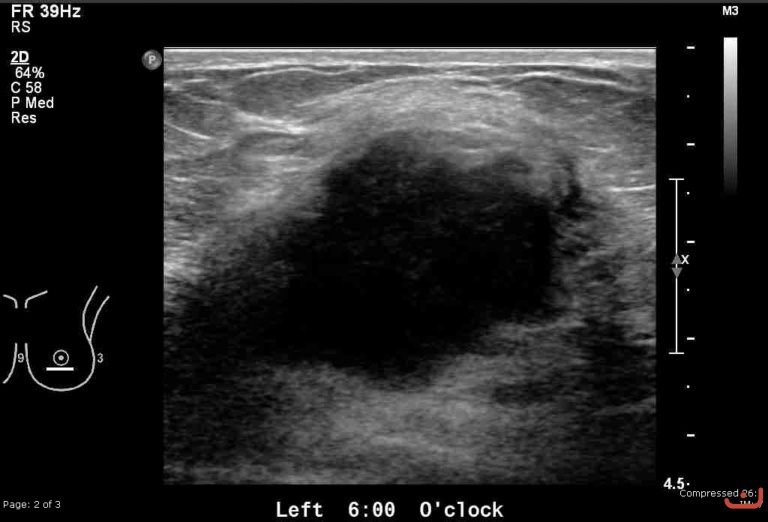

Malignant solid mass

Date

Thursday, 30 April 2015

File size of the original image

158.98 KB (768 x 522 px)